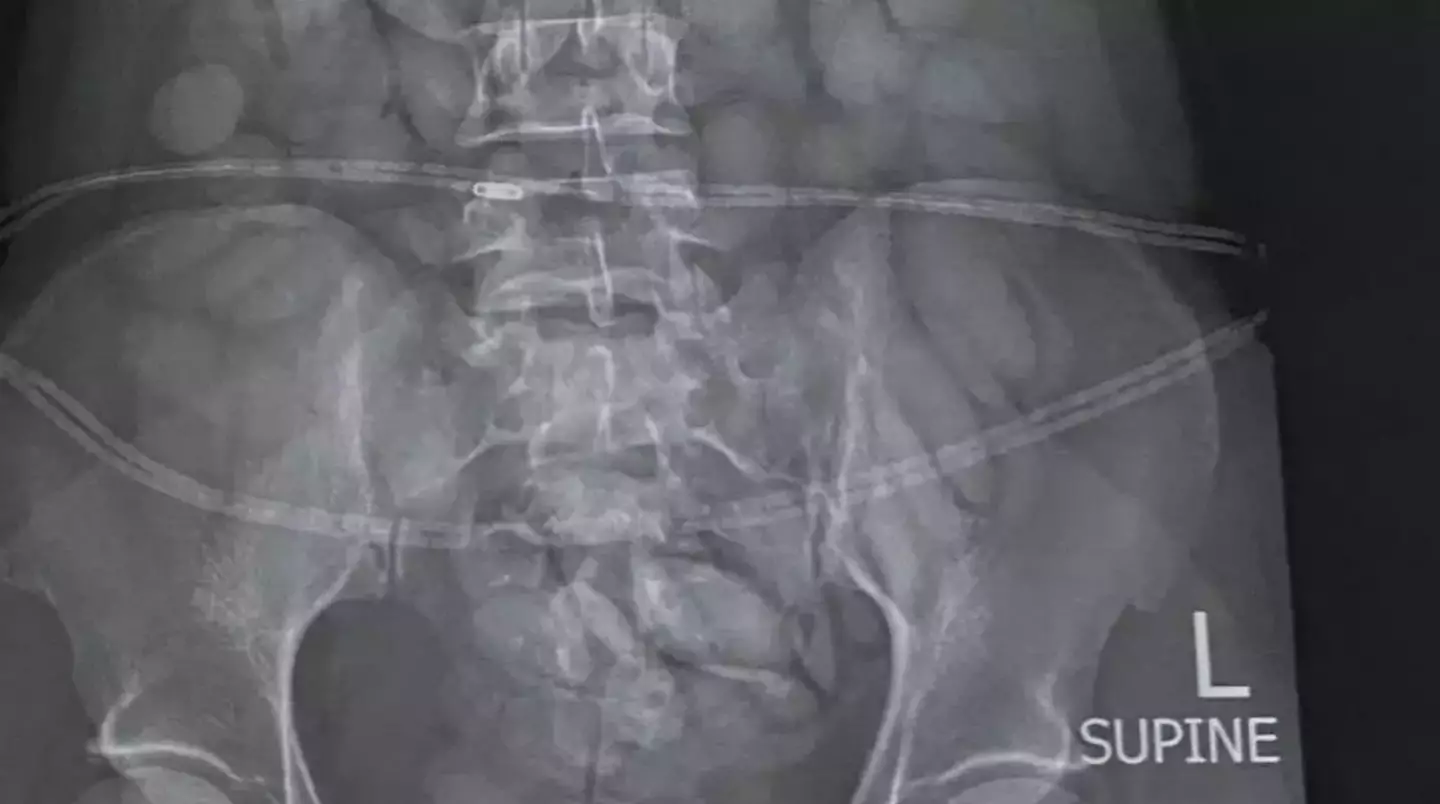

So, when the 30-year-old arrived, she was arrested and an X-ray instantly detected a number of foreign objects in her stomach.

Under police guard, she was then forced to 'release' 68 'bullets' of what is suspected to be cocaine.

Authorities say that the pellets weighed a combined total of about 850g.

Brig Athlenda Mathe, a spokesperson for the police, said: "The team immediately intercepted the drug mule as she was making her way through immigration. She was immediately arrested, taken to a local hospital where a medical X-ray confirmed and detected foreign objects in her stomach.

"The drug mule has released 68 drug bullets from her body. The estimated weight of the drugs is 850 grams. The value of the drugs cannot be determined at this stage."